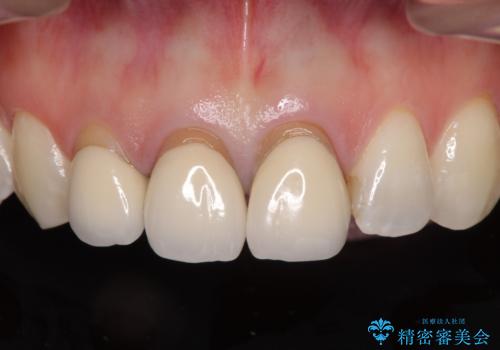

前歯は一部根管治療を行った後にオールセラミッククラウンに補綴することとしました。

審美面と合わせて機能面も改善され、患者様には大変満足していただきました。